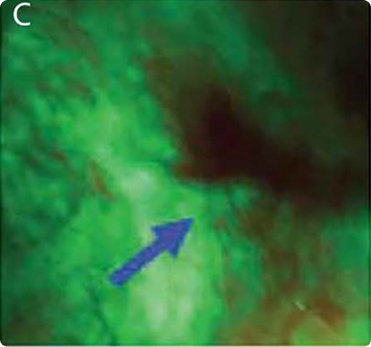

MONITORING TREATMENT SITES WITH VELSCOPE AND DNA PLOIDY: EARLY DETECTION OF RECURRENT ORAL CANCER​

Image A: White-light image of a well-healed scar from squamous cell carcinoma (SCC) on the left lateral tongue.​

Image B: The anterior aspect of the same scar under fluorescence visualization, showing a dark brown area of fluorescence loss.​

Image C: Follow-up after 12 months, with the same area exhibiting a persistent and enlarged loss of fluorescence. After 20 months, a biopsy from the region of fluorescence loss was diagnosed as carcinoma in situ.​